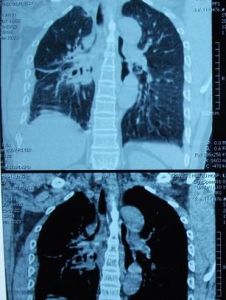

1.X線檢查

通過X線檢查可以了解肺癌的部位和大小,可能看到由於支氣管阻塞引起的局部肺氣腫、肺不張或病灶鄰近部位的浸潤性病變或肺部炎變。